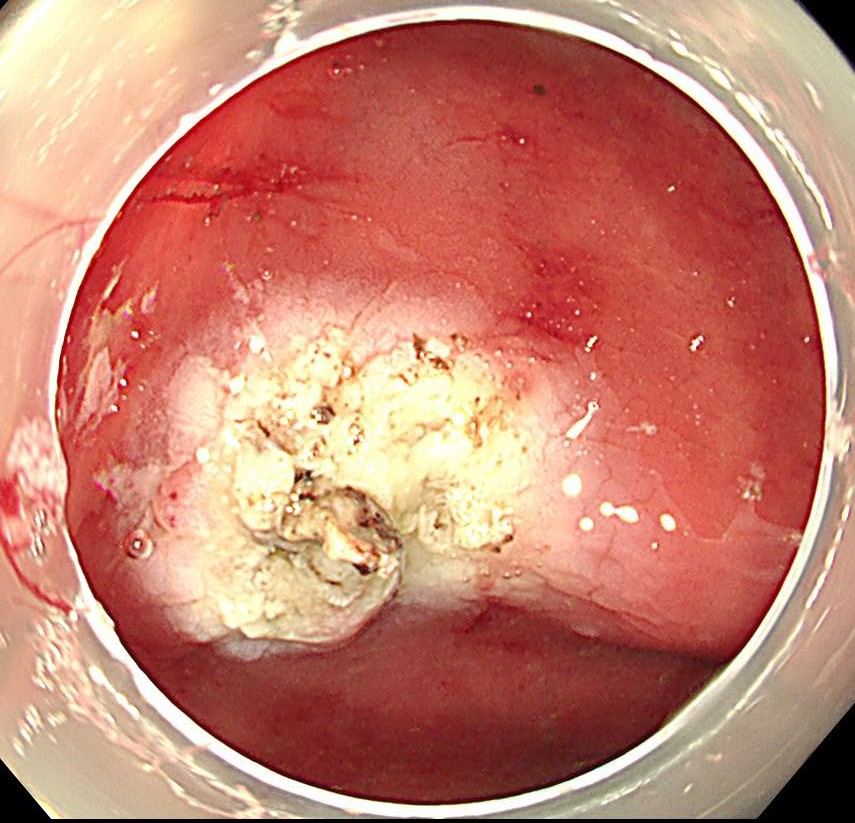

まずはコアグラスパーを用いてソフト凝固60で止血します。

止血確認後、クリップで血管縫縮し、完全止血します。